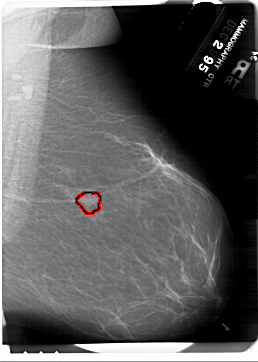

A_1372_1.RIGHT_CC

RIGHT_CC LINES 6871 PIXELS_PER_LINE 4966 BITS_PER_PIXEL 12 RESOLUTION 43.5 OVERLAY

FILE: A_1372_1.RIGHT_CC.OVERLAY

TOTAL_ABNORMALITIES 1

ABNORMALITY 1

LESION_TYPE MASS SHAPE LOBULATED MARGINS OBSCURED

ASSESSMENT 4

SUBTLETY 3

PATHOLOGY BENIGN

TOTAL_OUTLINES 1

BOUNDARY